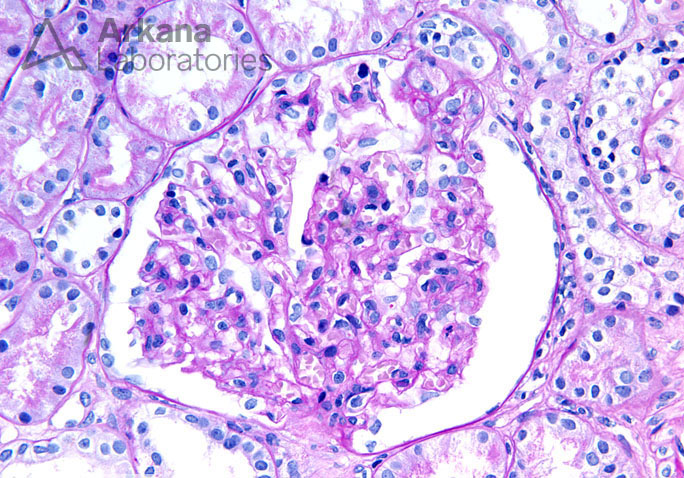

Enlarged Glomerulus with a FSGS Tip Lesion on PAS